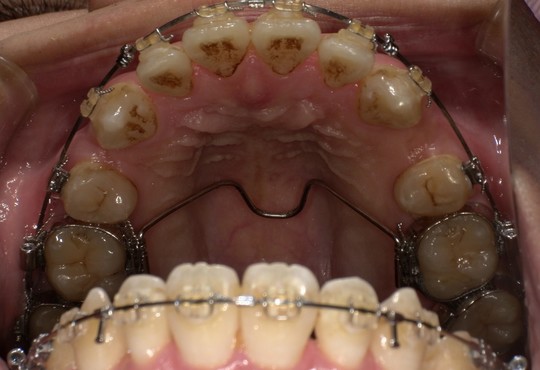

年齢:70代男性

治療内容:エアーフローによる歯の着色汚れ、ステイン除去

治療期間/通院回数:1回

費用: ステインコース 8,800円

リスク・副作用

①効果には個人差があり、着色汚れによっては一度に取りきれない場合があります。

施術後数時間以内に、着色効果の強いもの(コーヒー・紅茶・喫煙など)を摂取すると、歯に色素沈着が起こる可能性があります。

パウダーの刺激により歯ぐきから出血する可能性があります(痛みはほとんどありません)。